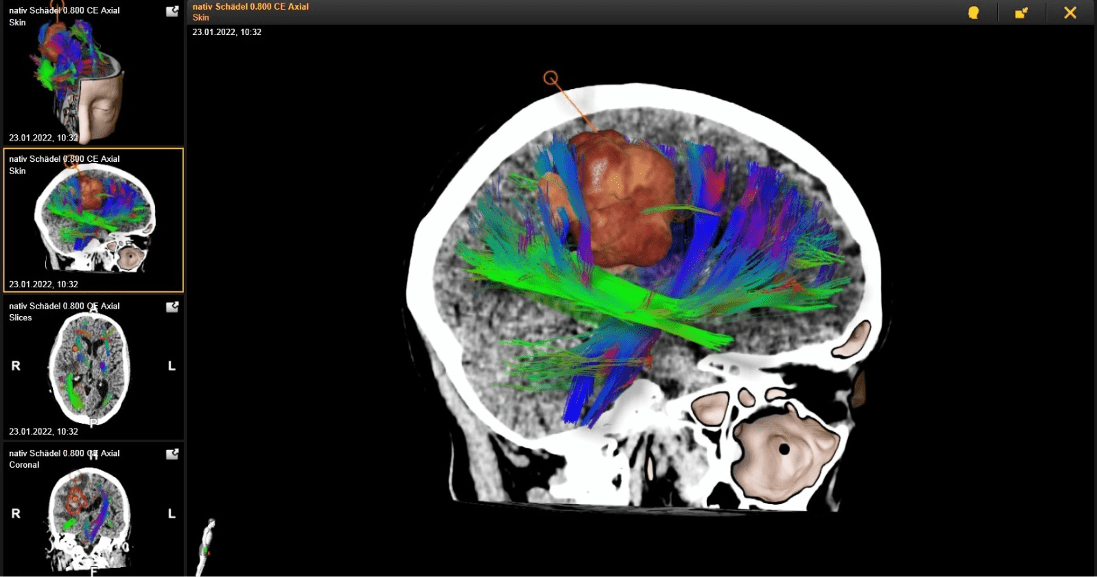

Glioblastomas account for 51 % of all primary malignant central nervous system tumors Their established therapy consists of a gross total resection when safely feasible, followed by adjuvant radio-, chemo- or radiochemotherapy and application of tumor treating fields. However, the current therapeutic regimen seems rather ineffective, since the survival of patients suffering from glioblastoma averages less than two years.

This lecture will provide an overview on the current clinical management of glioblastomas, on the future therapeutic perspectives as well as on the scientific contribution of the presenter in this field.